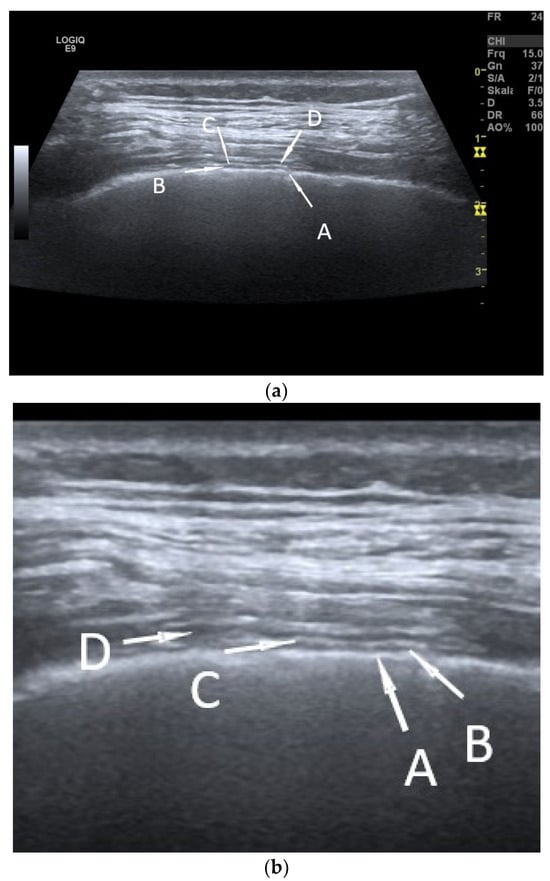

| Fibrothorax | Extensive and dense fibrosis of the visceral pleura, with fusion of the visceral and parietal pleural layers, no lung sliding. |

| Encapsulated pleural effusions | Round, smoothly circumscribed hypoechoic or anechoic masses. No evidence of macrovessels in CDI. Non-enhanced in CEUS. |